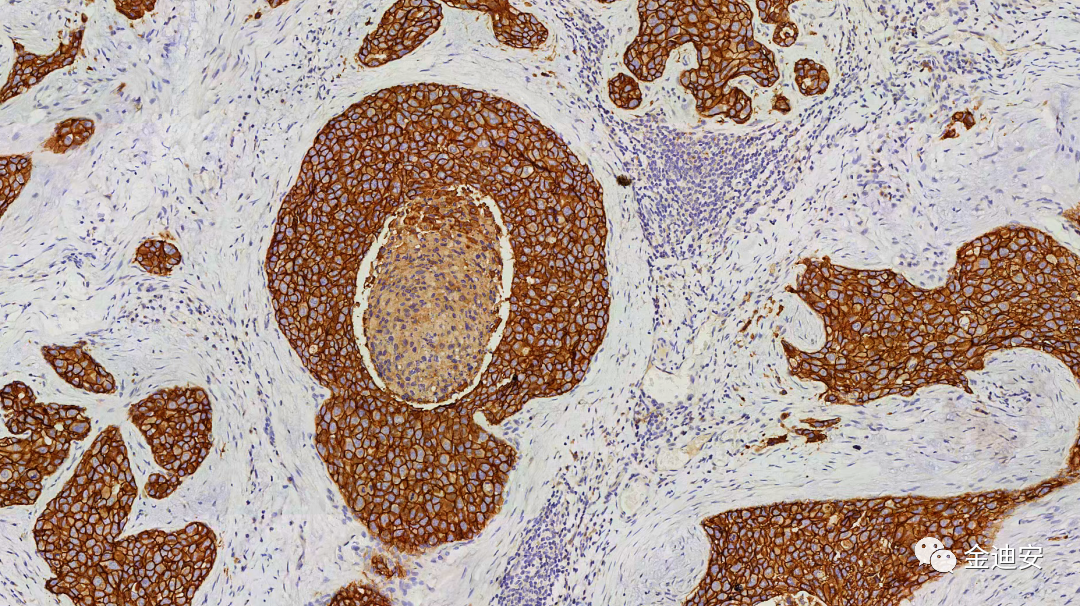

【染色效果圖】

E-Cad